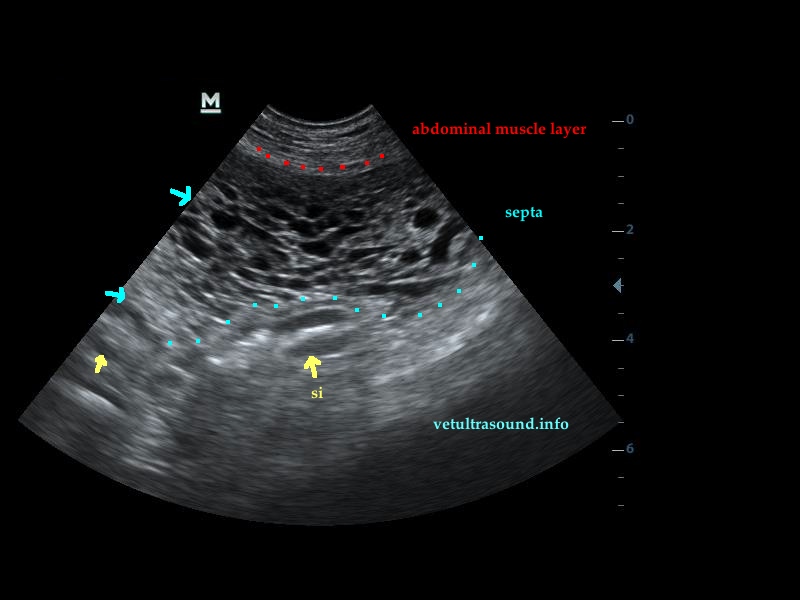

Findings: Signs of uremic gastritis. Ascites (transudate) and septa surrounding all the abdominal organs were found. The kidneys were small in size and the resistive index of the interlobular arteries was low.

Diagnose: Encapsulating peritoneal sclerosis.

It is evident in dogs with Leishmania, history of surgery, septic peritonitis or chronic peritoneal foreign bodies.